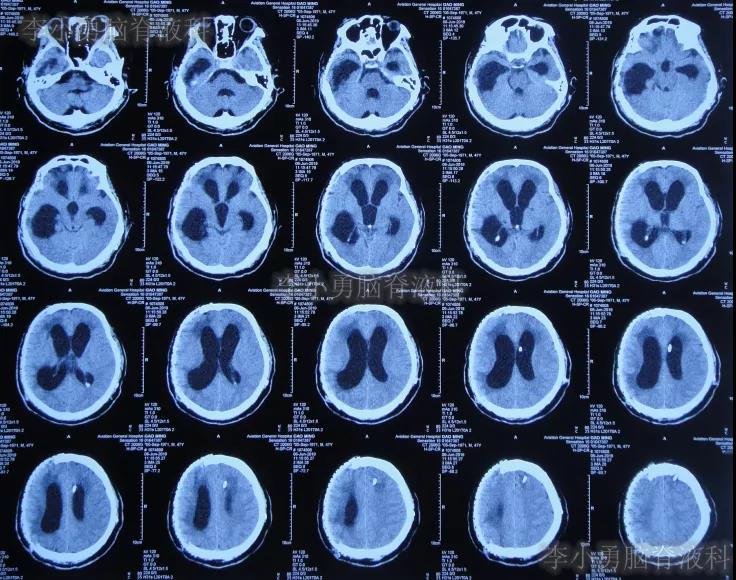

2018年8月17日(开颅术后37天),意识仍不清,查头颅CT示脑室扩张,脑膨出,有钙化(图-1);再次给予腰大池持续引流7天后拔除。

图-1:2018年8月17日头颅CT

2018年8月28日(开颅术后48天),查头颅CT示脑室进一步扩张,脑膨出加重(图-2);但意识还可以,未给予继续治疗。

图-2:2018年8月28日头颅CT